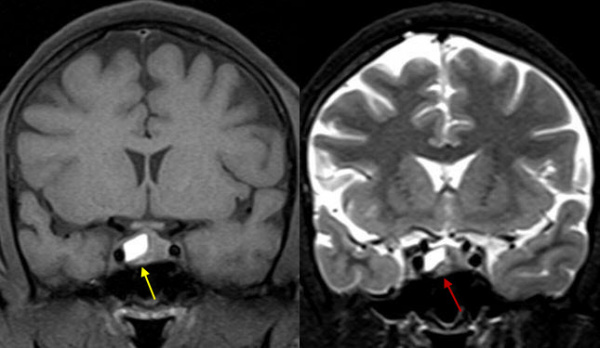

(Слева) Макропрепарат пациента, который умер от осложнений апоплексии гипофиза, коро-нальный срез через турецкое седло: геморрагический некроз аденомы гипофиза, распространяющейся в оба пещеристых синуса.

(Справа) МРТ, постконтрастное Т1-ВИ, режим подавления сигнала от жира, сагиттальный срез: у мужчины 48 лет с острым возникновением головной боли, гипопитуитаризмом и зрительными нарушениями отмечается периферическое контрастное усиление крупного объемного образования селлярной/супраселляр-ной областей - апоплексия гипофиза. Обратите внимание на увеличение размеров турецкого седла.